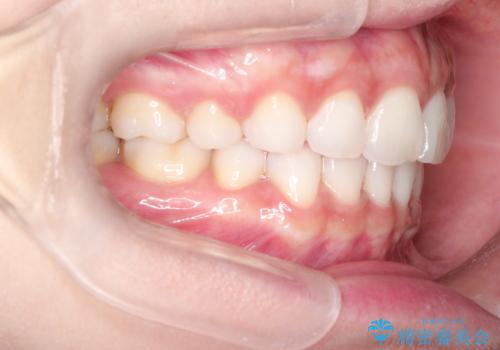

出っ歯を改善した後に真っ白な歯に 矯正歯科治療と審美歯科治療